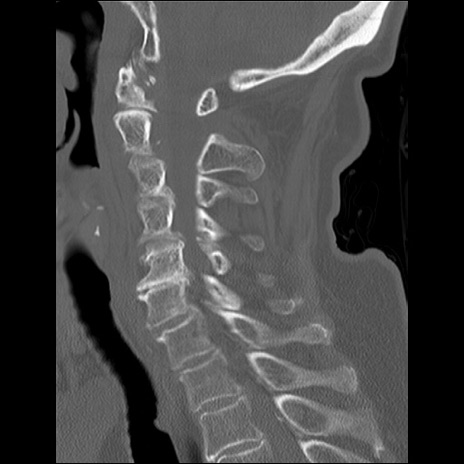

症例48 頚椎CT(矢状断像)

頚椎CT